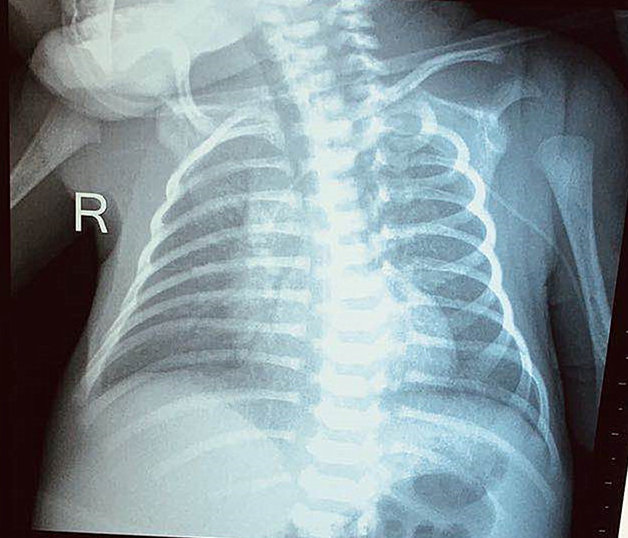

小小的生命背后,是一个家庭的未来与希望。竭力帮患儿突破“营养供给”这项难关,成为了新生儿重症监护室团队共同的心愿。综合考虑患儿的各种情况后,团队决定为患儿采取PICC置管术。9月5日,新生儿重症监护室联合静疗小组,在静疗小组组长、肿瘤科王静护士长的协助下成功为患儿置入PICC。缓缓流淌的营养液通过PICC管道顺利输入到患儿体内,医护人员悬着的心终于落下,得知消息的家属也终于露出欣慰的笑容。

PICC置管操作复杂,技术难度大,此次成功完成低体重早产儿的置管,是医院的又一项重大突破,大大提高了低出生体重儿的存活率,为新生儿临床救治创建了重要的生命通道,成为新生儿救治的又一项核心技术,标志着医院新生儿诊疗及护理技术再上新台阶。